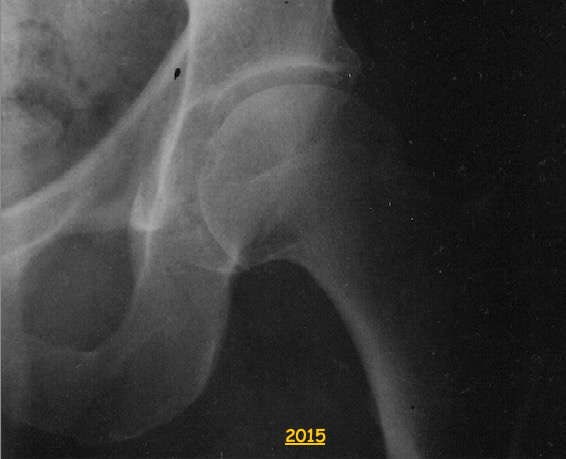

Passez le curseur ou le doigt sur l'image pour afficher l'état de la même articulation 10 ans plus tard.

L'articulation de la hanche fait intervenir les os soudés du bassin (ilium, ischium et pubis) et le fémur. Celui-ci est l'os le plus long et le plus solide du corps humain. La réduction de l'espace articulaire correspond au vieillissement du cartilage.